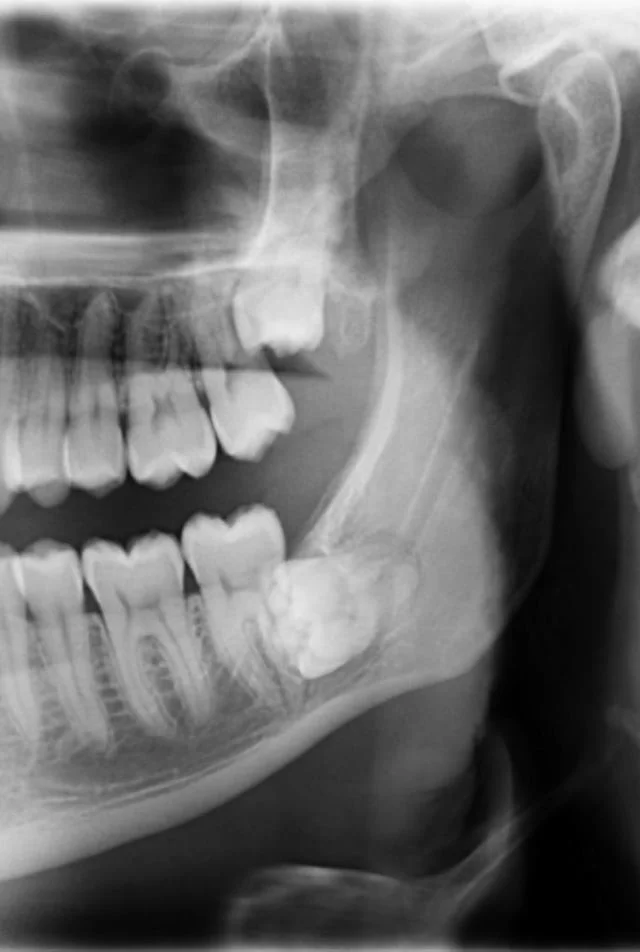

19. «Рентгеновский снимок зубов моего шестилетнего ребёнка»

1. «В прошлом месяце я пришёл на чистку зубов к стоматологу. Я упомянул, что чувствую онемение в одном из зубов. Я был в ужасе, когда увидел опухоль, которая разрушает челюстную кость»